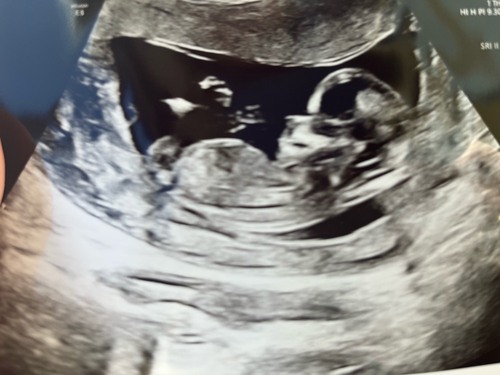

Aangezien de vorige gesloten is, bij deze nog een keer de foto. Met precies 12 weken! Ben benieuwd 😊

Het is een foto van de benen.. maar zal er tussenin ook iets te zien zijn? ...

Lijkt vrij hoog te zitten dan. Ik zou eerder denken aan de navelstreng🤭

Ik zie alleen een hele overduidelijke nub goed hoor dus bestudeer ze niet zo lang en goed met bewerken enzo als nubster🤭

Wat ik wel doe is dat ik kijk naar nub én skull theorie. Daarmee samen kom ik bij jou uit op een meisje💗

Je laatste foto is dan weer wat verwarrend, maar dat kan ook de navelstreng zijn aangezien we de hoek niet goed kunnen zien waarin de foto genomen is🙃